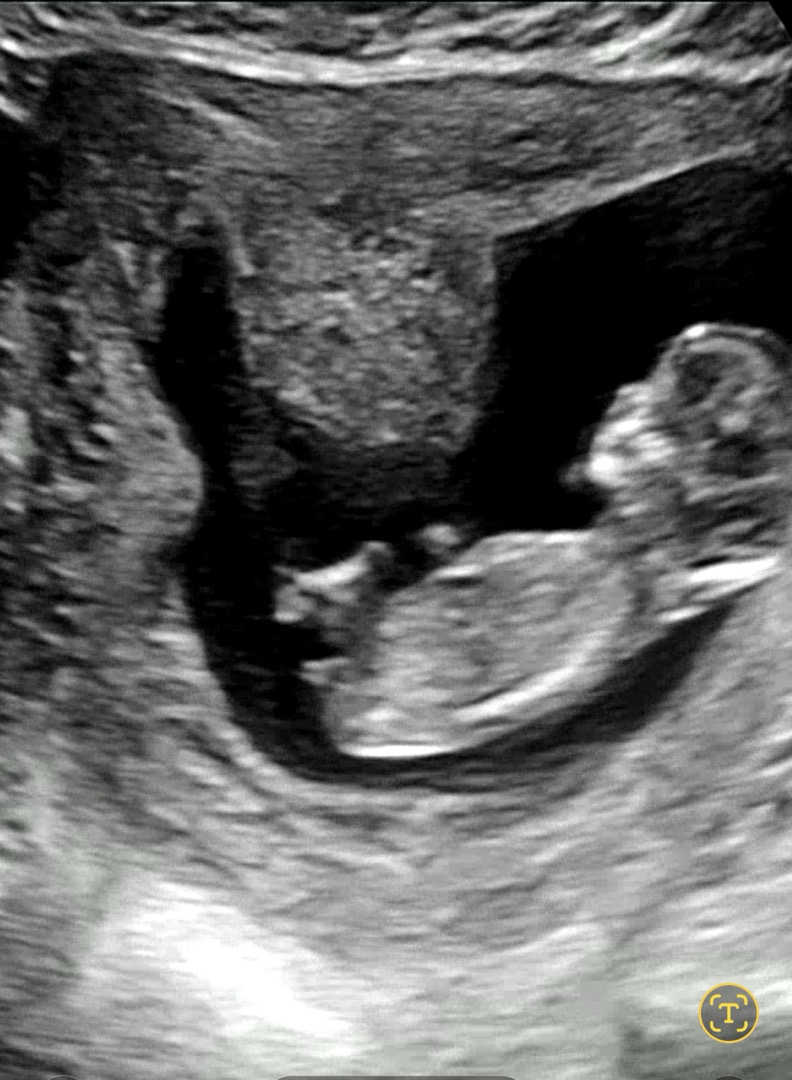

12주2일차 각도법 궁금해요!

12주 2일차 초음파에요 성별좀 봐주세요!!

딸이요!